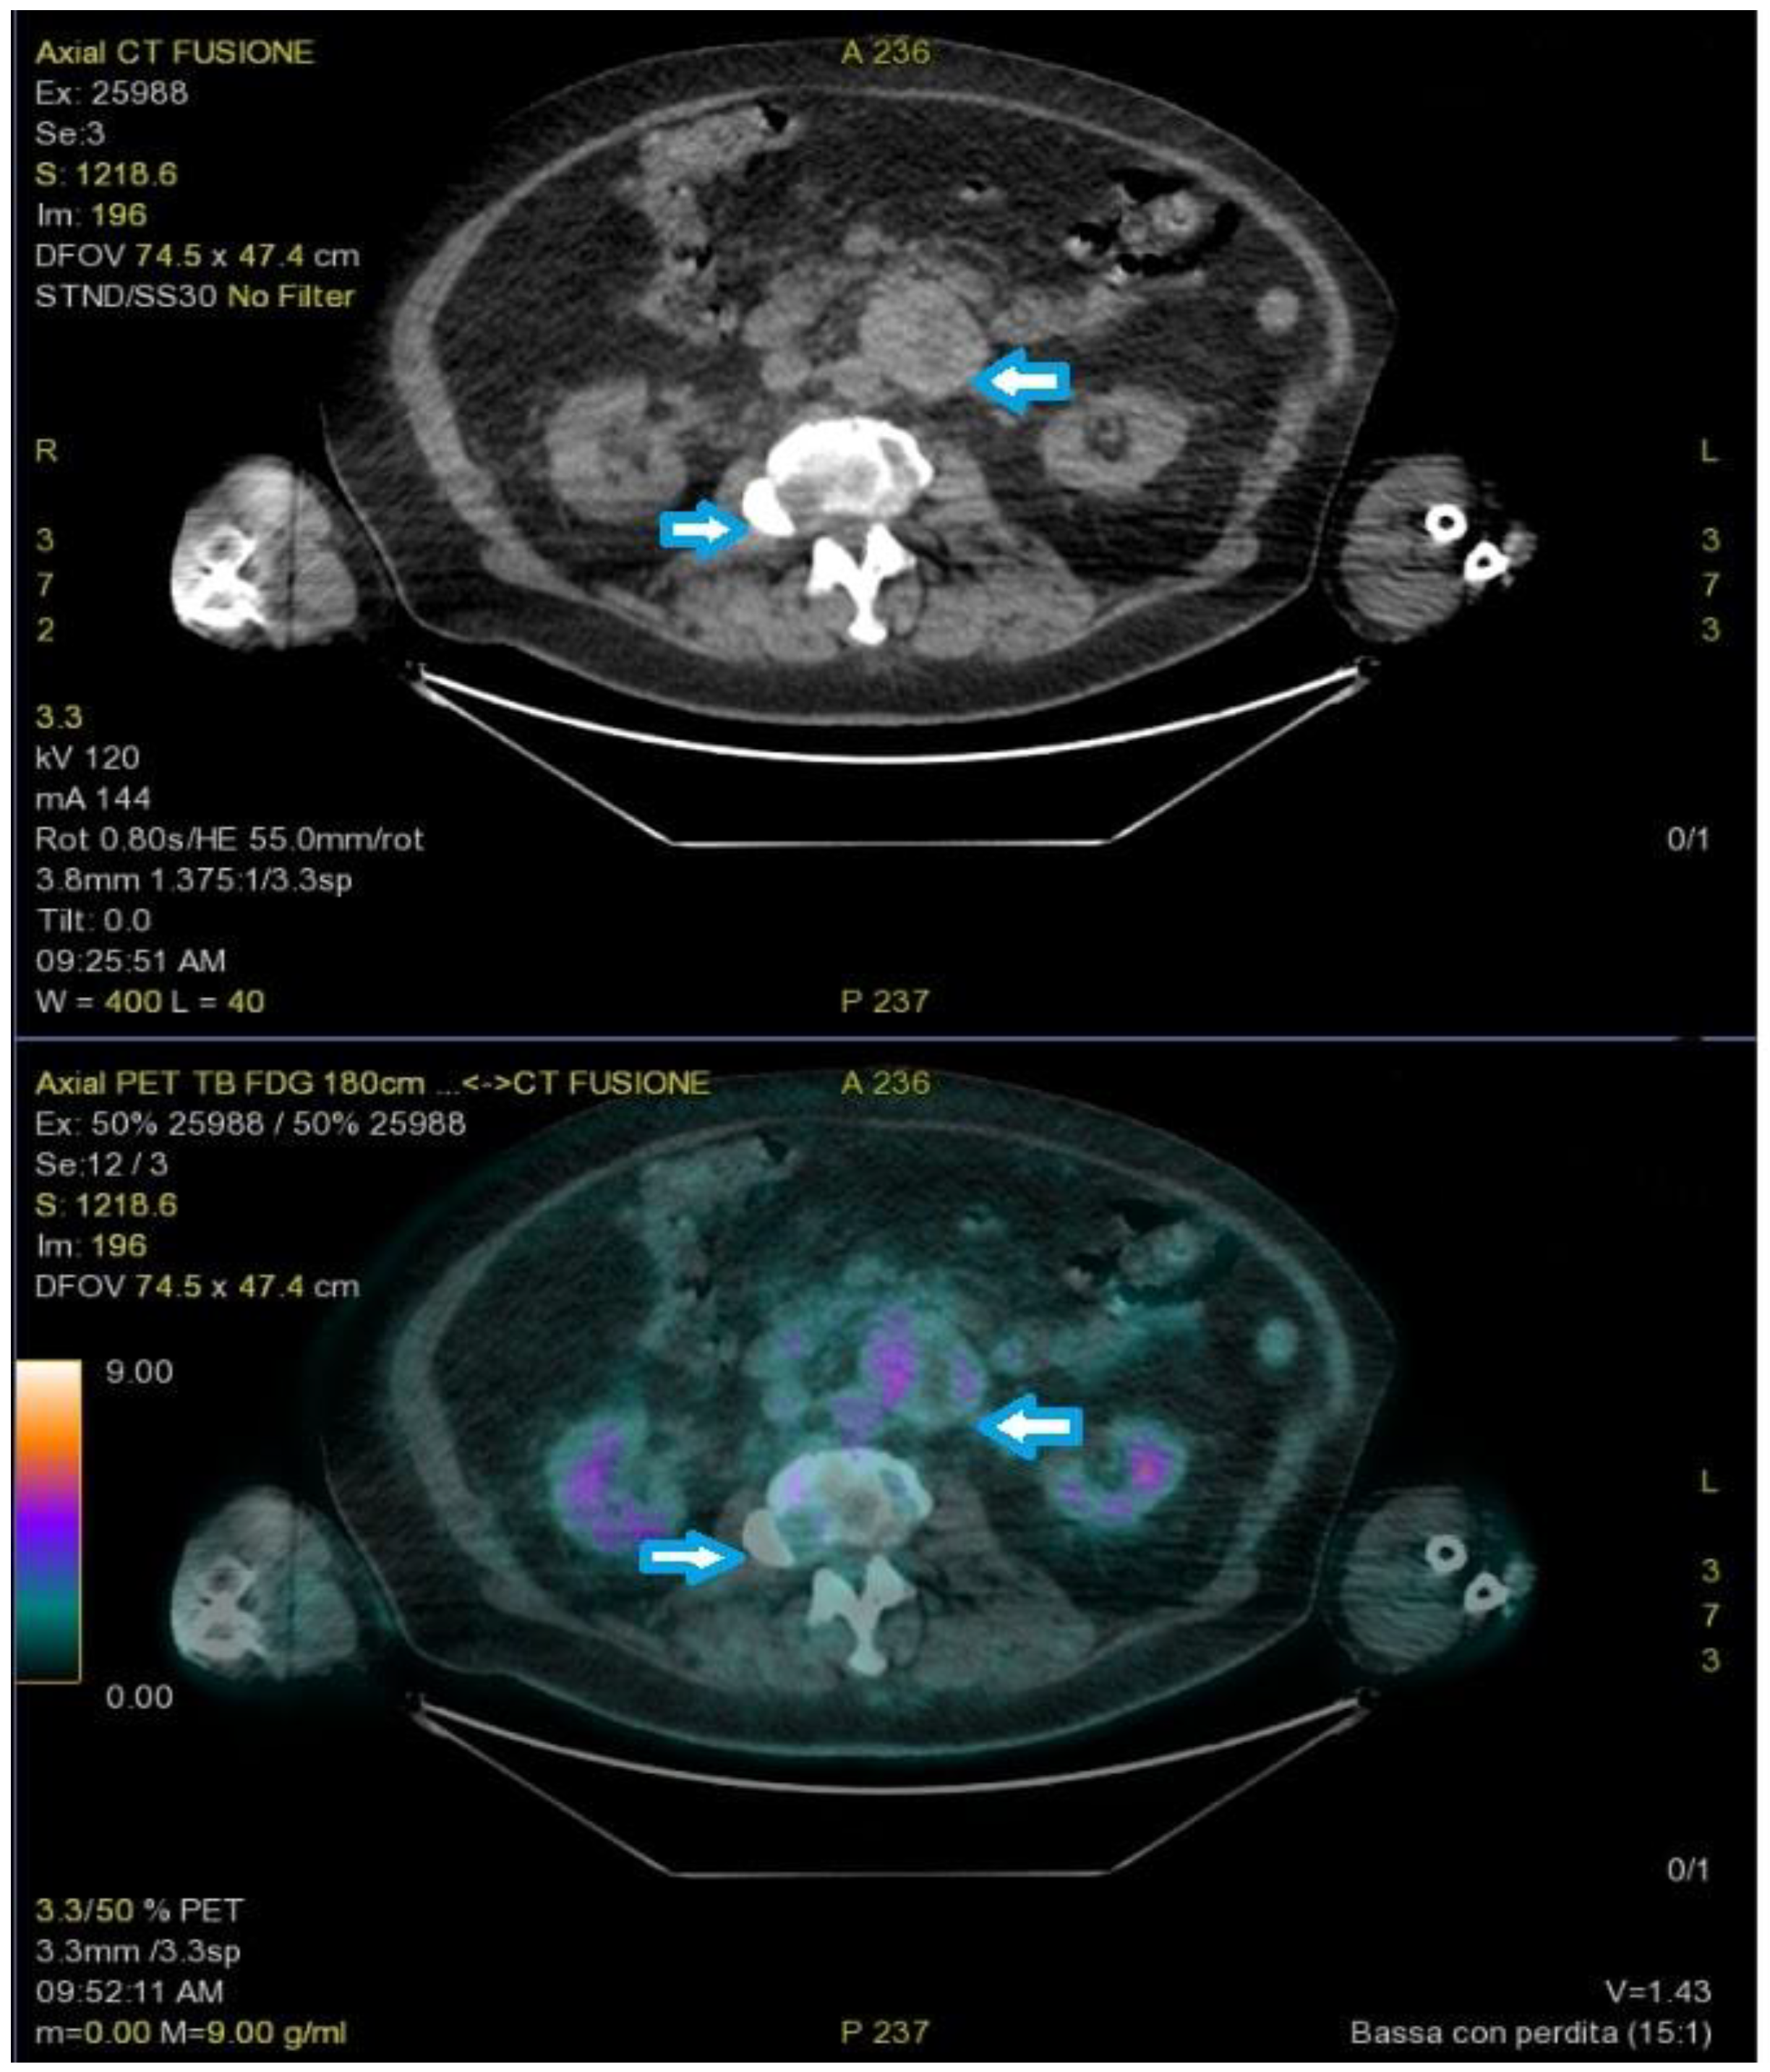

2. Case Report